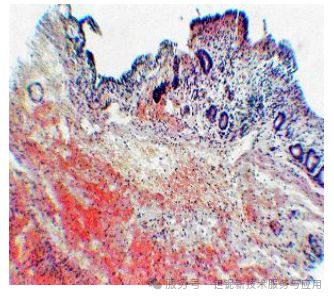

犬胆道造影:通过胆囊穿刺注入 20-30% 稀土TaO₄混悬液(5-8 ml),术中实时成像并取组织样本(苏木精 - 伊红染色),对比泛影葡胺对黏膜的影响(图 10、图 11)。

犬胆道造影中,30% 稀土TaO₄可清晰显示直径≥7 mm 的结石,肝内胆管分支显影分辨率达 0.5 mm(图 9)。相比之下,泛影葡胺组黏膜出现大面积坏死,而 稀土TaO₄组仅见轻度淋巴细胞浸润(图 10、图 11)。

图10.犬胆囊注射LOT 30 %凝胶混悬液后,苏木精和伊红染色,100倍放大。